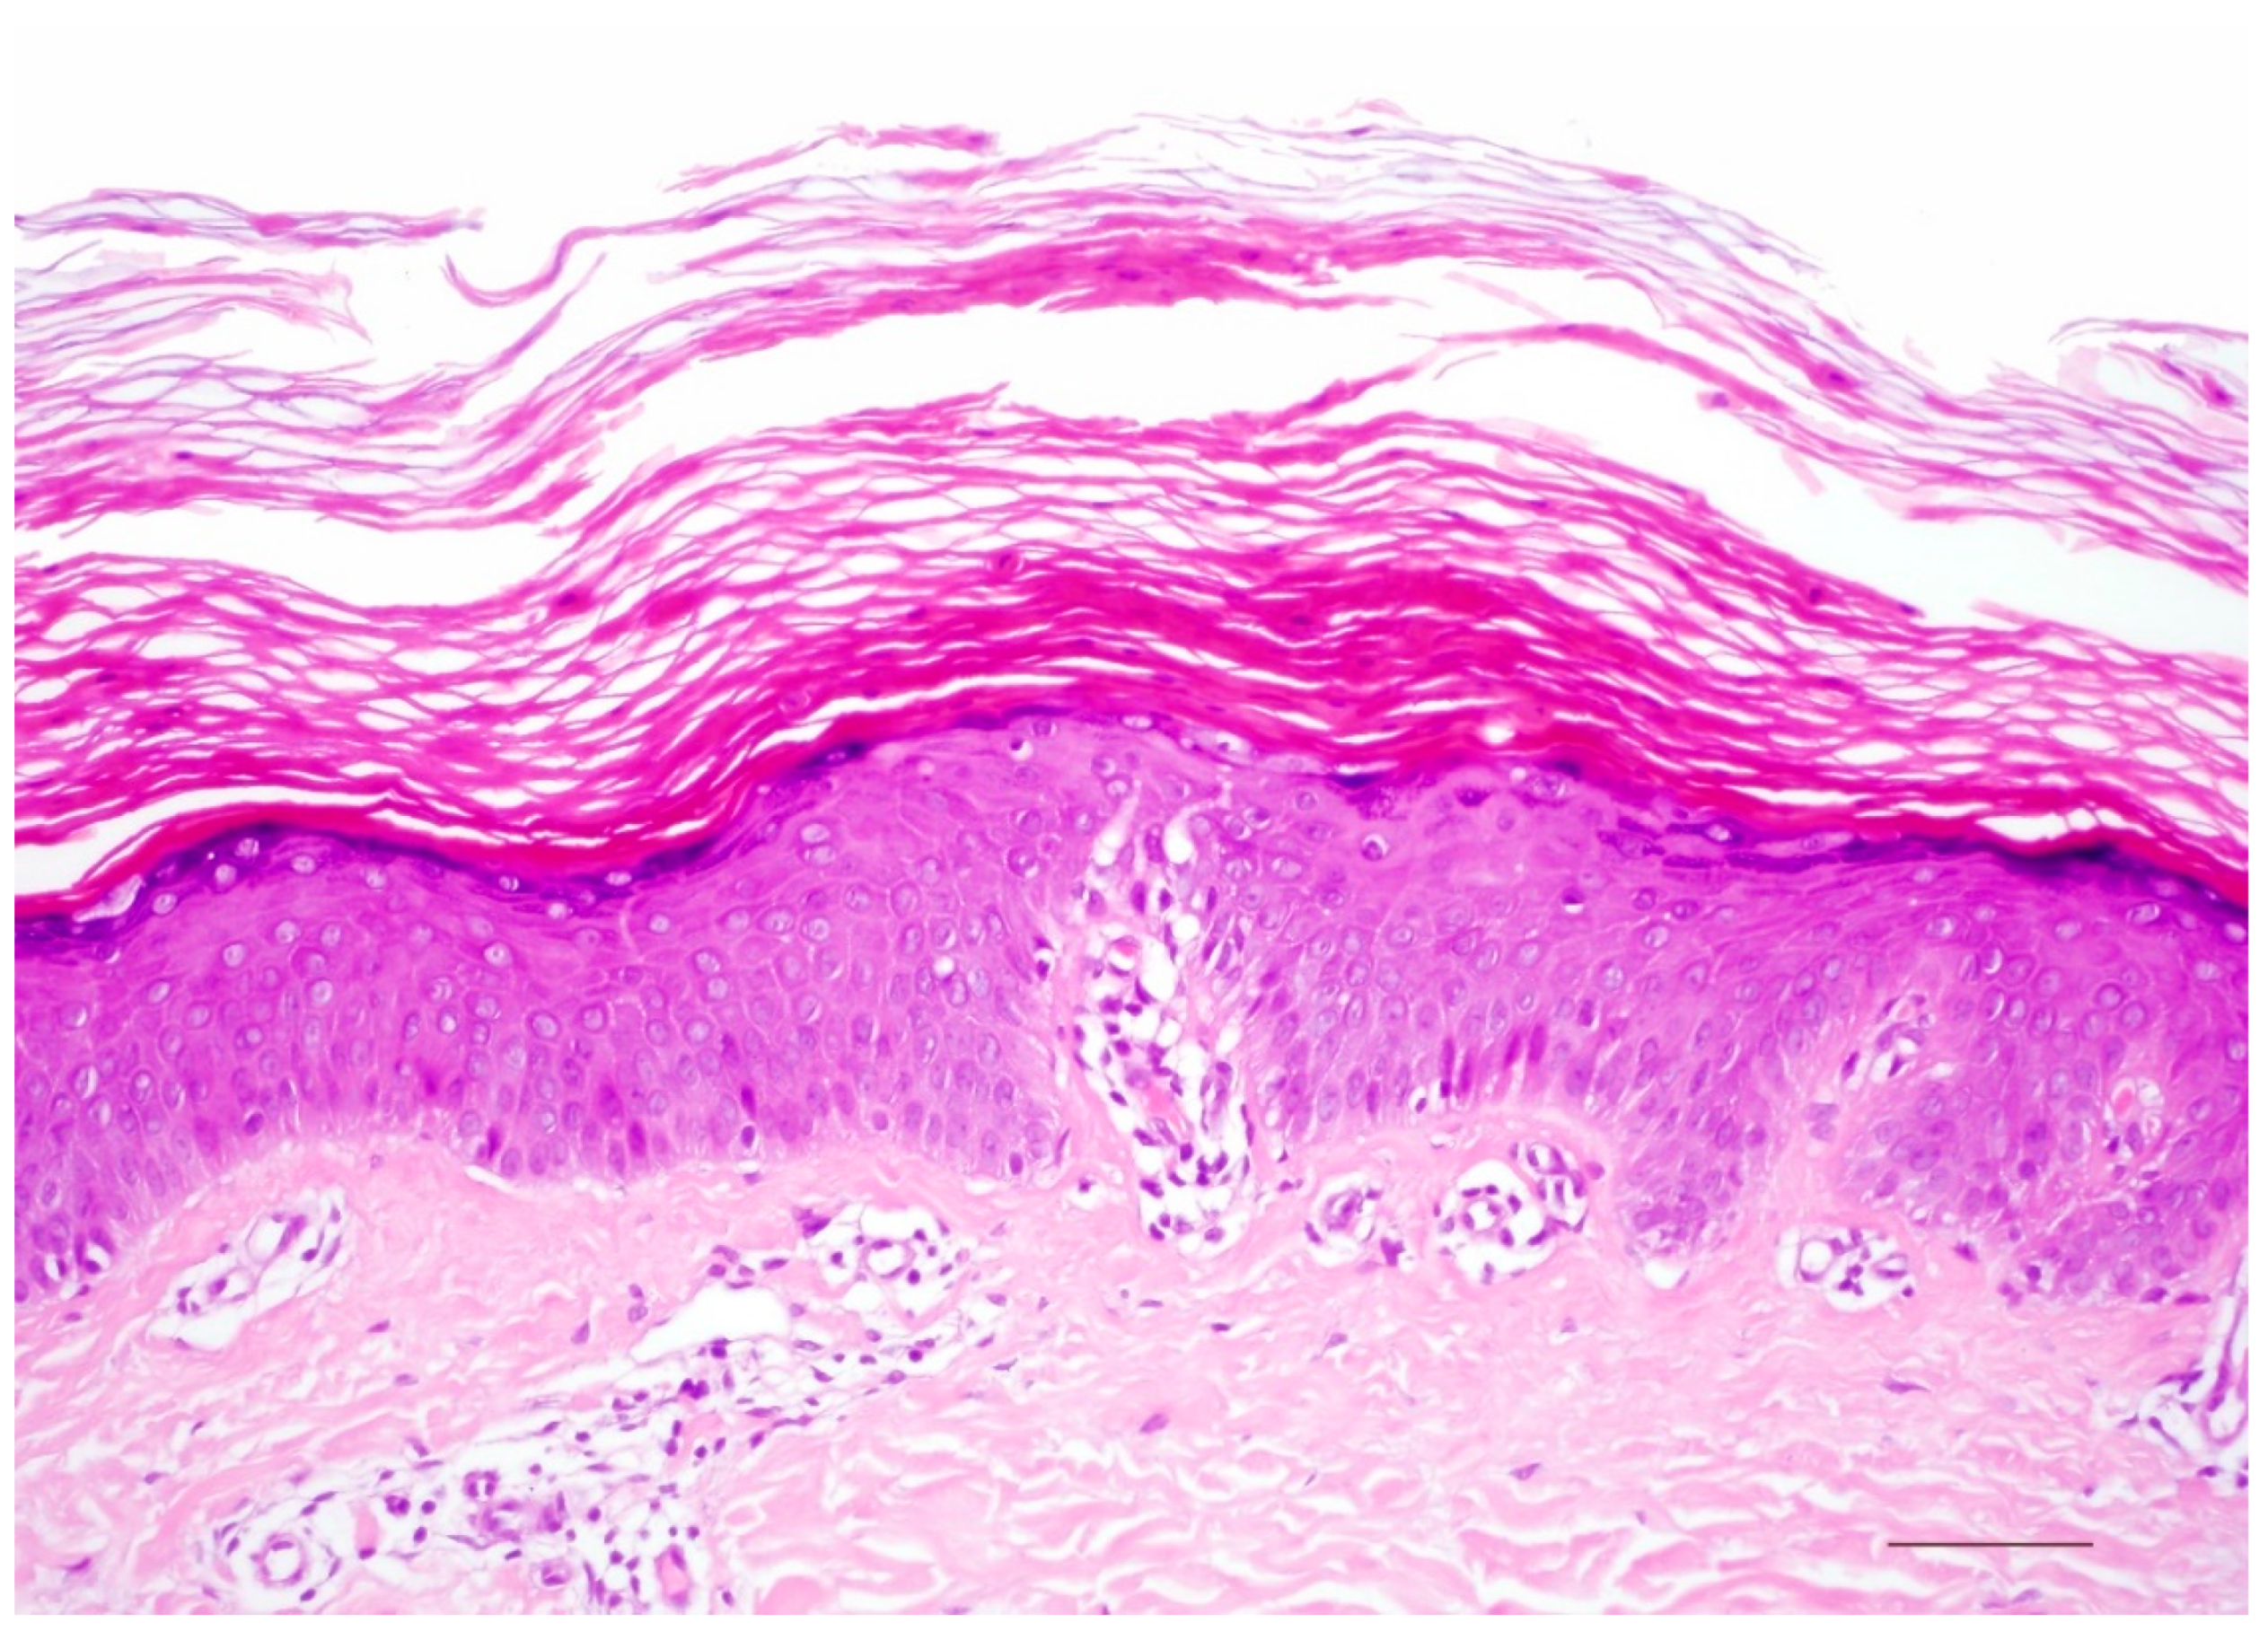

4. Autosomal Recessive Congenital Ichthyosis

4.1. Histology